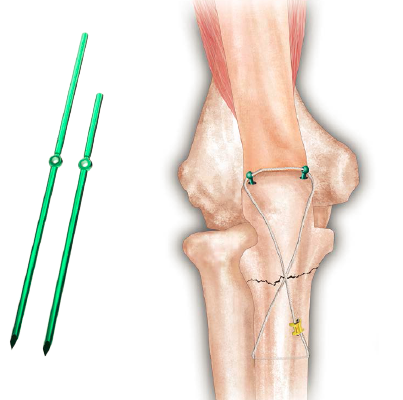

中段孔骨針

針體桿部開孔結(jié)構(gòu)設(shè)計(jì):結(jié)合金屬纜索做骨折張力帶固定,可以為骨折處提供更加穩(wěn)定的內(nèi)固定,豐富臨床選擇;

主針體光桿設(shè)計(jì):快速拔出,避免二次傷害。

張力帶原理:加壓

張力帶技術(shù)最早是由Weber BG推薦應(yīng)用到骨科領(lǐng)域。利用鋼絲張力帶固定時(shí)將鋼絲置于髕骨張力側(cè),使之在承受功能狀負(fù)荷時(shí),由于肌肉等收縮因素,使張力轉(zhuǎn)變?yōu)閯?dòng)力,產(chǎn)生斷端間軸向加壓,不產(chǎn)旋轉(zhuǎn)力,有利于內(nèi)固定的穩(wěn)定,允許早期活動(dòng)。Pauels首先把張力帶鋼絲作為一種骨折內(nèi)固定方法應(yīng)用于臨床。

股四頭肌的牽拉,皮質(zhì)表面的張力轉(zhuǎn)化為關(guān)節(jié)面的壓力,增加了骨折端的穩(wěn)定性。